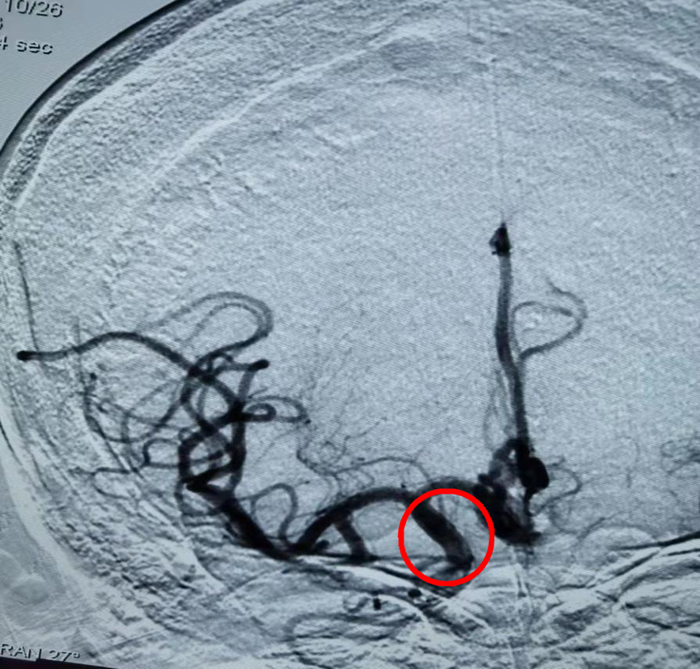

取出24.53mm血栓

取栓术后显示:右侧大脑中动脉、大脑前动脉血流恢复完好